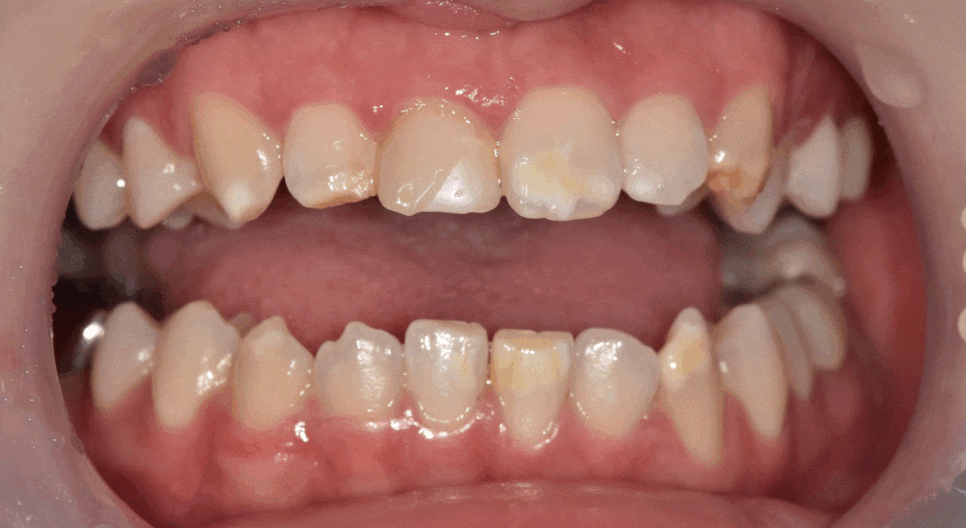

이 환자분은 하얀 반점 때문에

마음대로 웃지도 못한다고 하셨어요.

입안을 보니, 하얀 반점이 치아의 절반 이상을 덮을 만큼 퍼져 있습니다.

치아 절반 이상을 덮은 하얀 반점